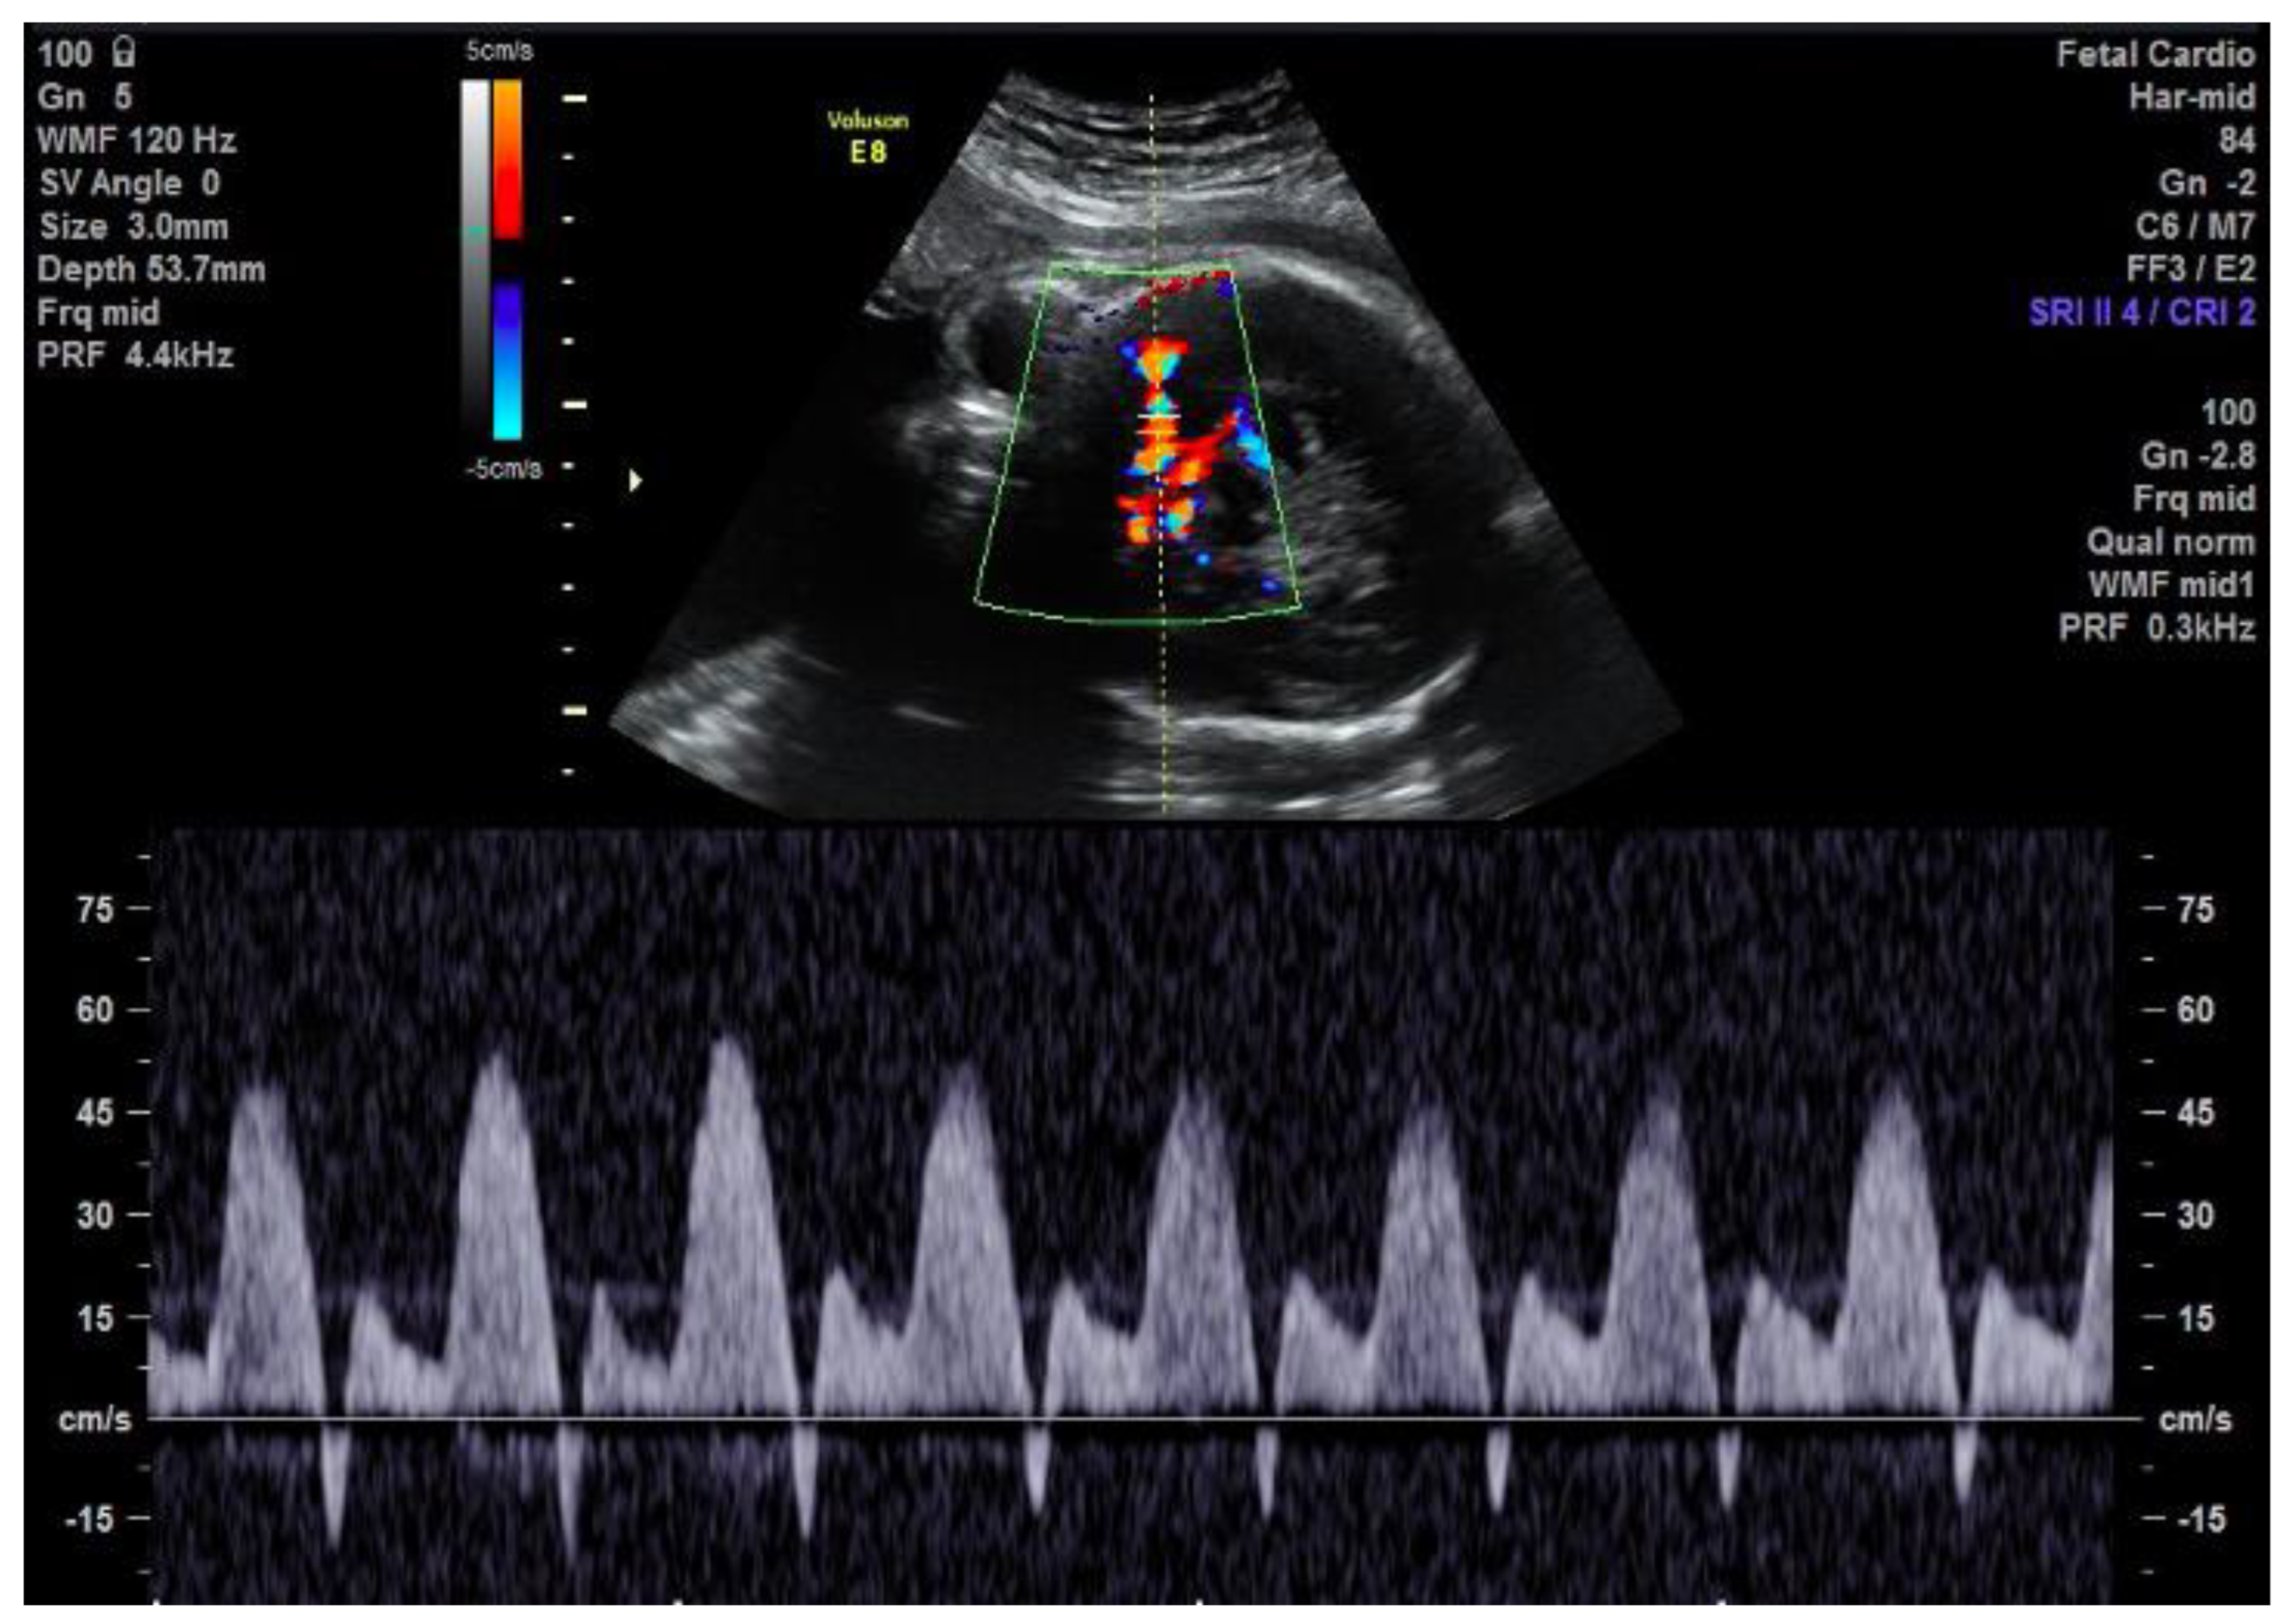

2. Case Description